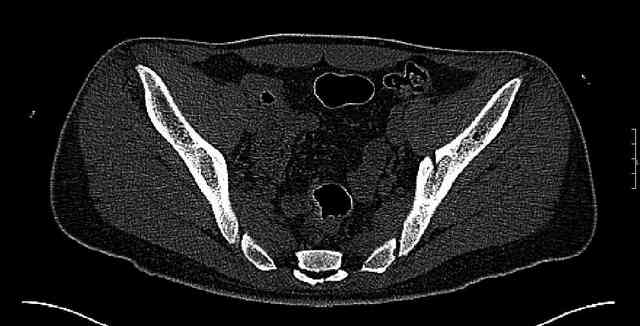

The joint is non-concentric as the head appears to be either "following the caudal segment", or the dome component is displaced from the tethered head... or so it seems... and he's young... so, many fracture surgeons would recommend reduction and fixation.

So we must decide preoperatively which part is the displaced segment?

It's difficult to know from these few selected images which component of the injury (was before and now) should be deemed the "soon to be mobile"

segment. It's my best guess that it is the caudal portion and there exists a healing fracture line somewhere thru the posterior column...one image

suggests it. If true, its early healing/union should be disrupted, and the resultant fragment mobility then allows accurate reduction.

Some more images. Does it help to guess which part of the acetabulum is displaced?

Normal appearing SI joints and a healed posterior column limb... my bet's on caudal segment displacement.